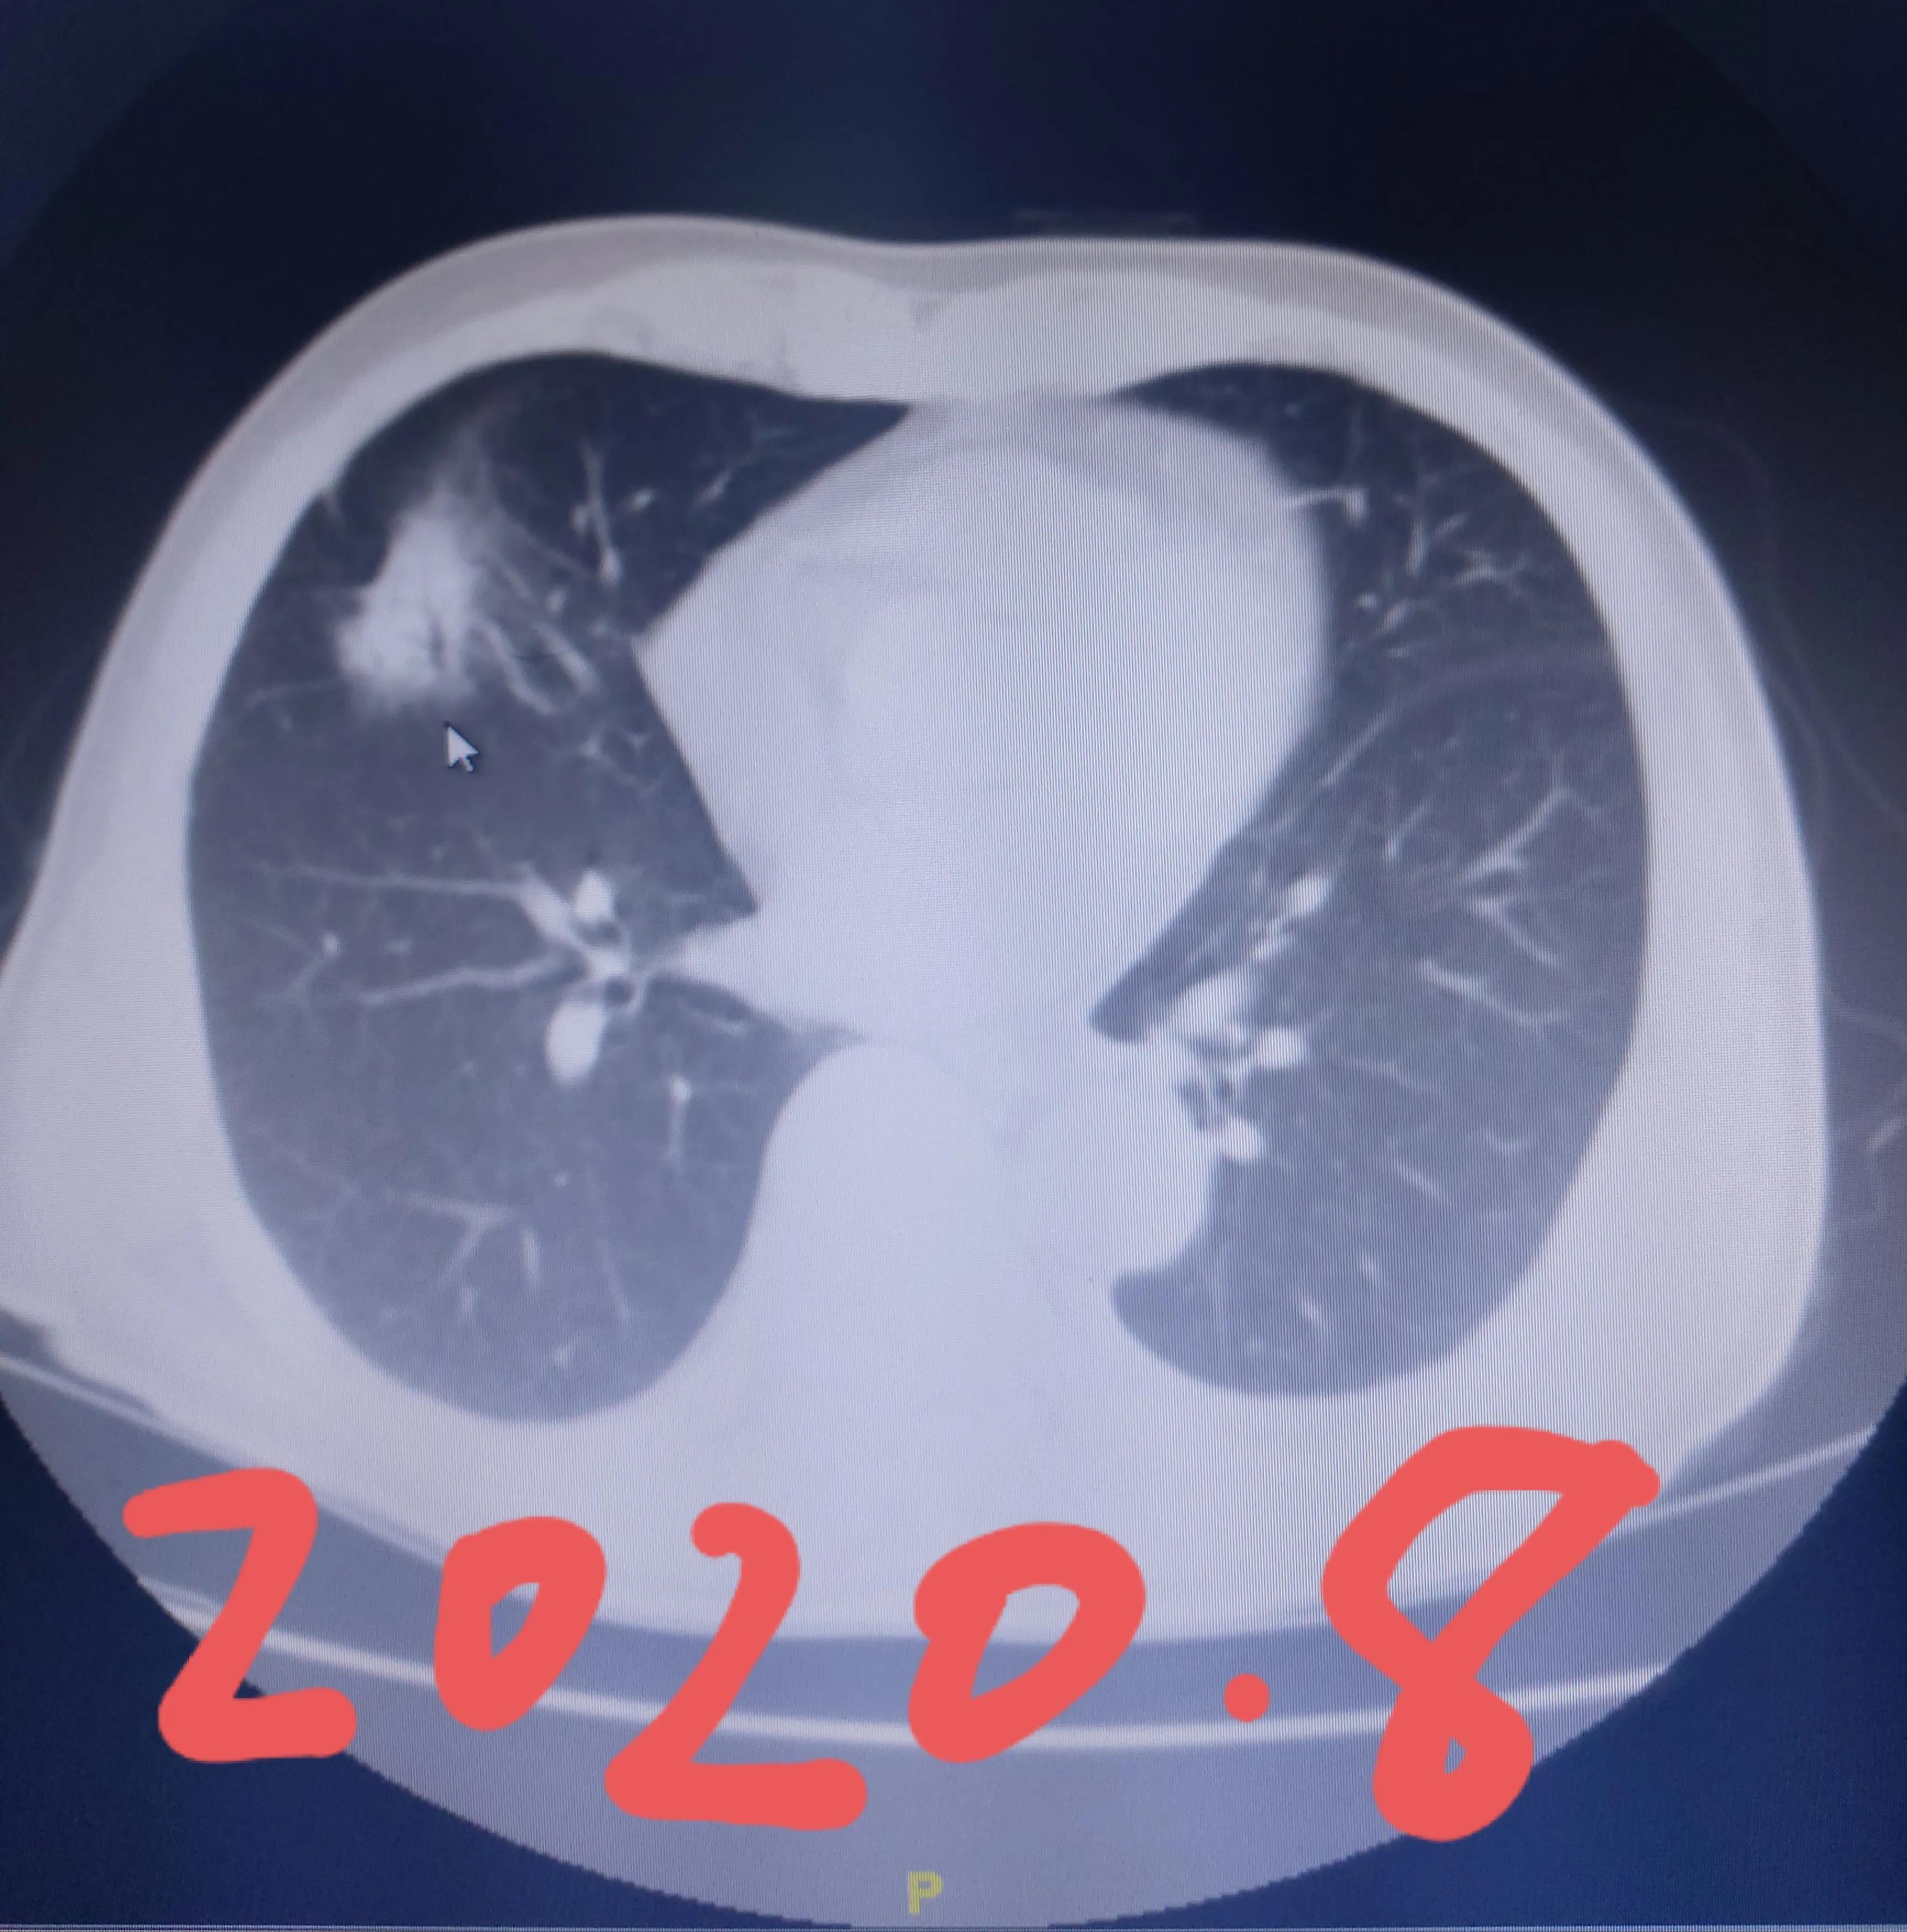

昨天应邀到神经内科参加全院专家会诊,我在去会诊之前,按照我的工作习惯,在电脑系统里面查看这位患者的影像学资料,也就是先预习一下,这位患者今年74岁,在2016年,我们医院电脑系统显示发现了右肺的结节,接下来就是2020年的8月,这个结节长大了。中间这4年的时间,在我们医院里面是没有资料的。

在全院专家制定了下一步诊疗计划后,大家让把患者以及家属请到示教室,坐下来再了解一下具体的情况。到我发问的时候我问家属,在4年半前就已经发现了肺部结节,但直到4年后才进行治疗,当时是怎么样考虑的?家属告诉我说在2016年的时候发现了这个结节,先采取消炎的方法,之后在其他医院复查片子,觉得比之前要变小,所以认为是一个良性的结节,就没有再复查,直到4年之后觉得咳嗽比之前频繁,再照片子才发现这个结节比以前增大,就确诊是肺癌了,不过已经没法手术了。